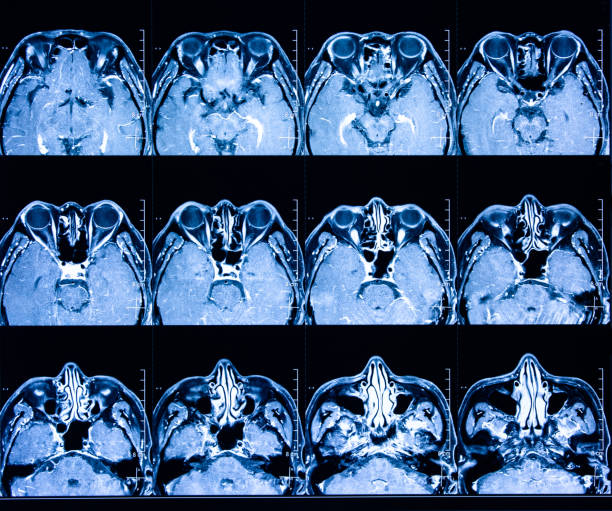

為了描述目的,患者按入組順序被賦予編號,并被連續(xù)分配到三組中的一組,每組三名。根據(jù)模型2分割,ICH體積范圍為0.1至54.9mL(平均ICH體積為23.5mL)。5名ICH患者受累于局限性腦葉,其余患者受累于基底神經(jīng)節(jié)或外囊深處。3名患者的ICH位于丘腦(圖1),1名患者的血腫位于多個腦結(jié)構(gòu)(即尾狀核、殼核和蒼白球)。平均而言,MSCs是在ICH后3天注射的。